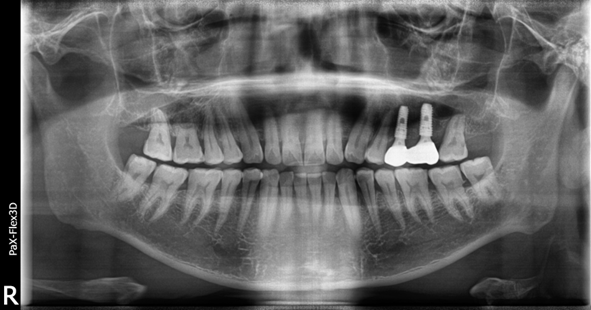

49세 남성

왼쪽 위 어금니 임플란트 식립

(전) 2021-12-28 (후) 2022-08-06

치아 뿌리에 심한 염증으로 치아 뿌리 끝에서 물혹이 발생한 질환(치근낭)이 관찰되어 치근낭적출술 후 뼈이식 진행한 환자분입니다.

발치 후 즉시 식립이 어려워 당일에 뼈이식까지 진행하고 3개월 후 지연식립을 진행했습니다.

치아 뿌리에 생긴 염증이 커지면 잇몸이 붓거나 잇몸뼈가 녹아 치아가 흔들리게 만들 수 있어 빠른 진단과 처치가 필요합니다.

39세 남성

상악동거상술 뼈이식 후 임플란트 식립

(전) 2021-12-07 (후) 2022-08-29

위 어금니 임플란트 진행 시 잇몸뼈가 부족해 광대뼈 안쪽 막을 들어올리고 뼈이식을 진행하는 상악동거상술을 시행한 환자분입니다.

상악의 경우 하악보다 잇몸뼈가 얇아 뼈이식의 난이도가 높고 최종 완료까지 걸리는 시간도 긴 편입니다.

따라서 성공적인 케이스를 많이 다뤄본 의사에게 시술받는 것이 좋은 결과를 가져올 수 있는 지름길입니다.